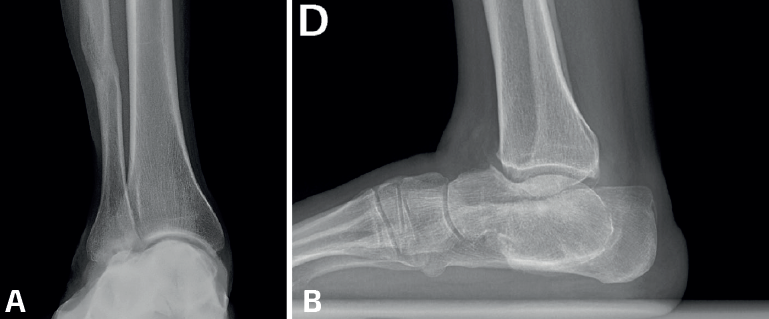

La mayoría de las coaliciones atípicas se diagnostican como hallazgos casuales al solicitar radiografías simples en pacientes con dolores en los pies, generalmente con deformidad en plano valgo. Las proyecciones convencionales –dorsoplantar y lateral– de ambos pies en carga suelen poner ya de manifiesto coaliciones atípicas como las talonaviculares y las calcaneocuboideas. Las proyecciones oblicuas son importantes porque suelen mostrar algunas coaliciones como las naviculocuboideas, las cuneometatarsianas y las coaliciones tarsales masivas. Las radiografías de ambos tobillos en carga suelen mostrar la consecuencia de algunas coaliciones tarsales masivas en forma de tobillo en cúpula (ball-and-socket)(13). Se han descrito varios signos radiológicos asociados a las coaliciones atípicas, como el “signo de la seta” en las talonaviculares, aunque algunas coaliciones atípicas presenten signos ya conocidos en las típicas, como el talar beak en las calcaneocuboideas o el del “oso hormiguero” en las naviculocuboideas(14)(Figura 1).

- Múltiples/Masivas: las coaliciones tarsales múltiples/masivas (dos o más de dos en el mismo pie) pueden presentarse como casos aislados no sindrómicos o asociados a otros problemas dentro de un síndrome (Figura 4). Se han descrito casos no sindrómicos de coaliciones combinadas calcaneonavicular, talonavicular y talocalcánea, con frecuencia bilaterales(26,50), y también afectando a la articulación tarsometatarsal(51). La mayoría son asintomáticas y algunas cursan con inestabilidad y entorsis de repetición en el paciente adolescente(50). En algunos casos observamos que la clínica depende del desarrollo de reacciones de estrés en los huesos limítrofes, como en el caso de un paciente con coaliciones tarsales talocalcáneas y naviculocuboideas y con dolor en la cuña intermedia(52). Aunque la mayoría mejoran con tratamiento conservador, existen casos publicados con cirugía de resección con mejoría de los síntomas(50,53,54,55,56,57). En muchas coaliciones múltiples/masivas del tarso, el tobillo (tibiotalar) tiene que adaptarse para poder trabajar como una tibiotalar y una subtalar a la vez, lo que conlleva un crecimiento adaptado a la función, formándose un tobillo cóncavo-convexo (ball and socket en la literatura anglosajona)(58)(Figura 5). En la mayoría de los casos, el hallazgo es casual y el paciente está asintomático. En línea con otras coaliciones, en los pacientes sintomáticos la clínica deriva de un pie plano-valgo. Las soluciones mecánicas consisten en el uso de plantillas con un buen gradiente supinador o en una cirugía de realineación mediante una osteotomía supramaleolar de cierre con base medial(59,60). En algunos pacientes con artrosis subtalar o tibiotalar avanzadas, los procedimientos de realineación pueden combinarse con artrodesis(61,62).